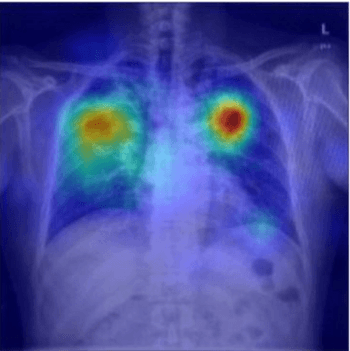

Applying a deep-learning model to a photograph of a chest X-ray can help providers in resource-poor areas diagnose the disease.